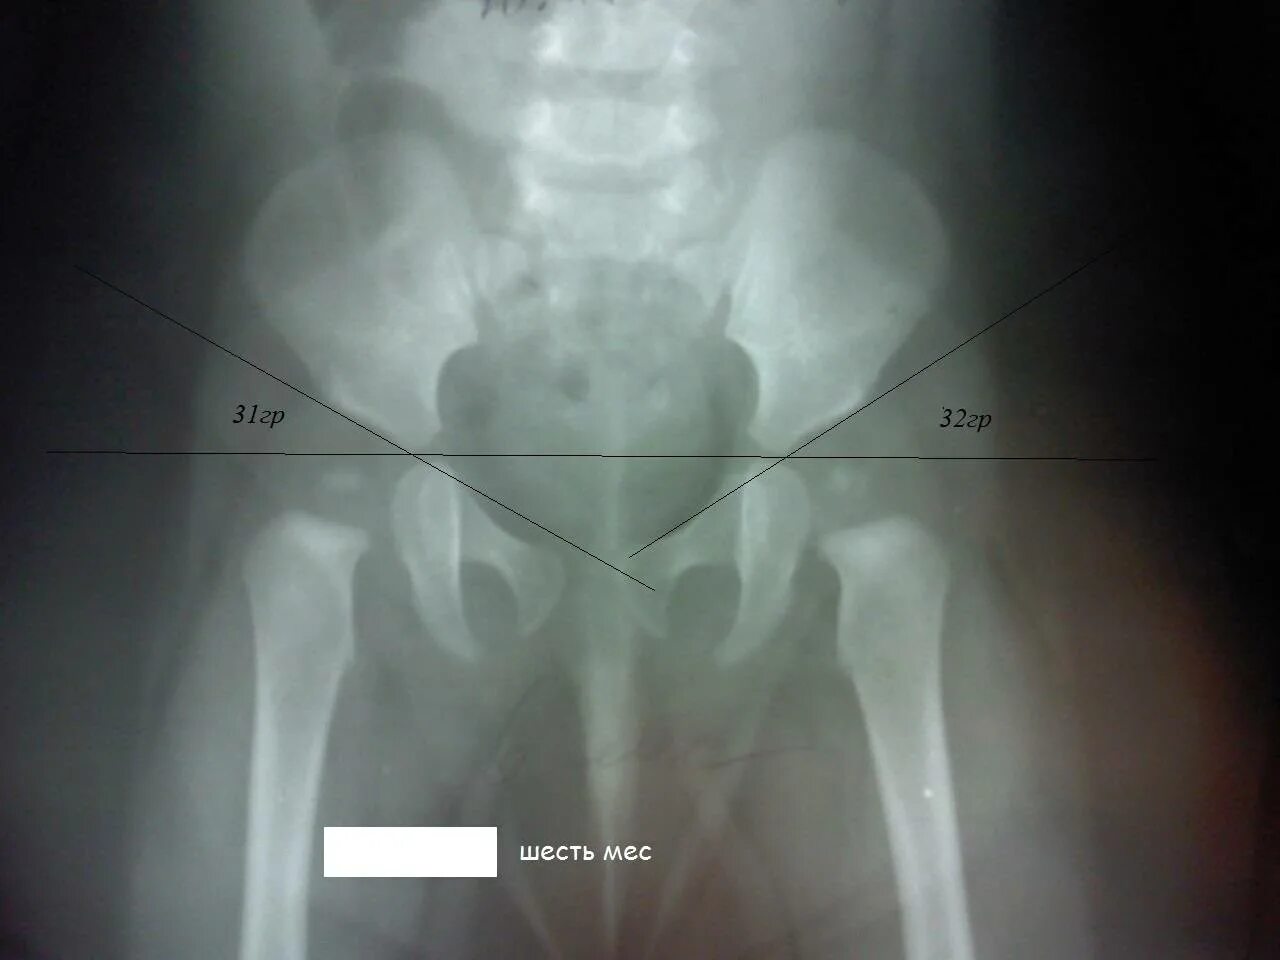

Тазобедренного сустава у детей